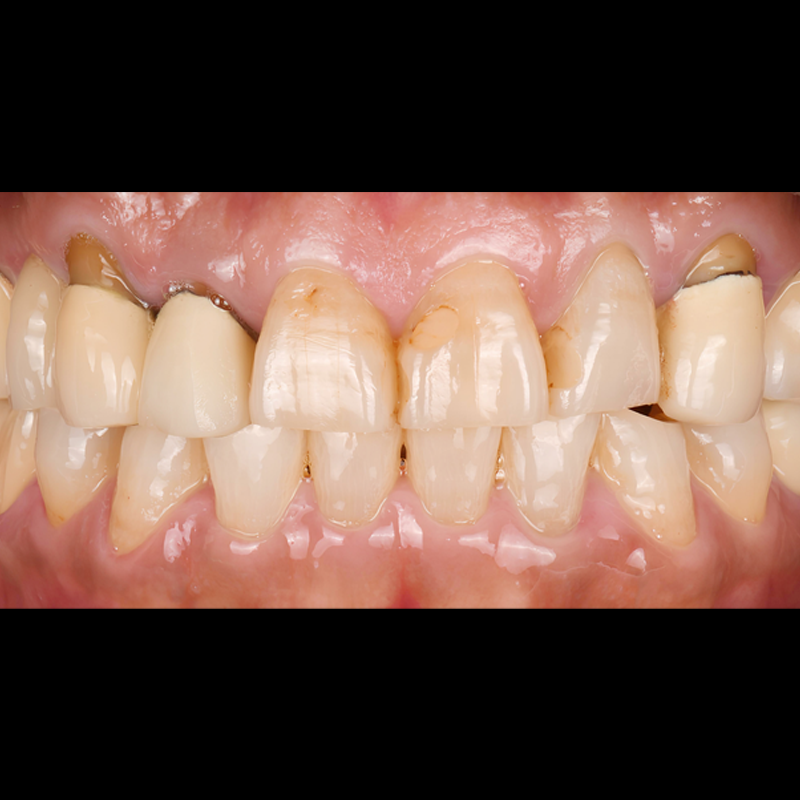

BEFORE AFTER

ルシネート前後の写真 2025.04.18

歯の着色治療のため、最小削除/無削除のルシネートを付着し、なめらかで自然な歯に仕上げました。